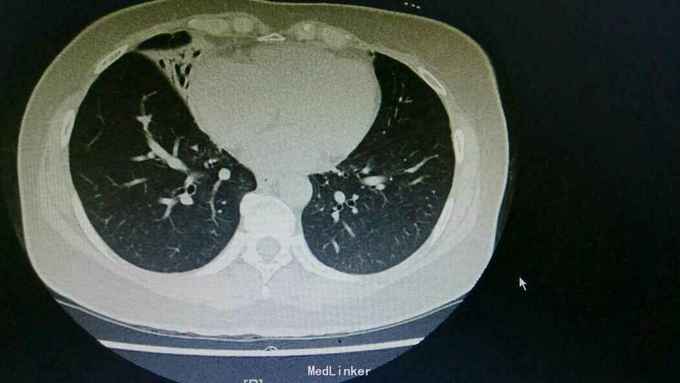

主诉:咳嗽8天,咯血6天。 病史:患者自诉8天前无明显诱因出现咳嗽,为刺激性干咳,未予以处理,6天前出现咯血,具体量不祥,为求诊治,入住我科。

查体:右下肺闻及湿性啰音,余无特殊。 辅查:胸部CT:右肺中上叶支扩并感染,双肺下叶磨玻璃影,考虑肺泡内积血可能。

诊断:支扩并咯血。 治疗:入院予以抗感染,止血,止咳化痰等治疗。